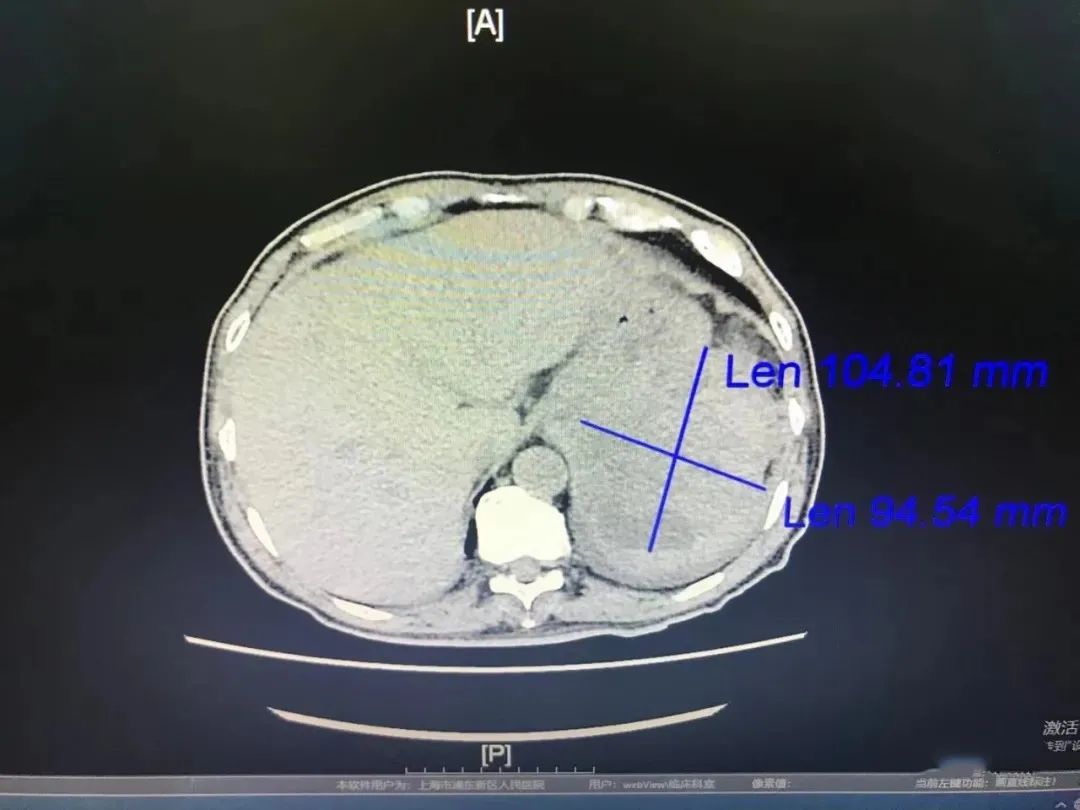

【浦人医·医者】一例胃间质瘤引发的思考

图片尺寸1080x810